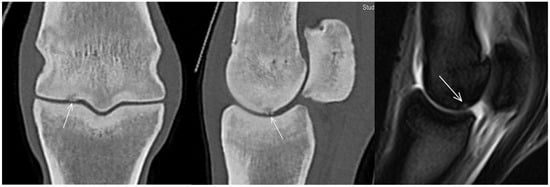

| Hypoattenuating lesion in the dorsal subchondral bone Subchondral bone thickening Dorsal/palmar half Increased attenuation in the trabecular bone Dorsal/palmar half Cone shaped/patchy Focal separated hyperattenuation | Hyperintense signal in the dorsal subchondral bone Subchondral bone thickening Dorsal/palmar half Decreased signal intensity in the trabecular bone Dorsal/palmar half Cone shaped/patchy Focal separated intermediate/low signal intensity | Radiolucent lesion Subchondral bone thickening Dorsal Increased trabecular bone opacity | |

| Medial/lateral condyle | |||

| Subchondral bone thickening Dorsal/palmar half Increased attenuation in the trabecular bone Dorsal/palmar half Hypoattenuating lesion in the subchondral bone Location | Subchondral bone thickening Dorsal/palmar half Decreased signal intensity in the trabecular bone Dorsal/palmar half Increased signal intensity in the subchondral bone Location | Increased opacity in the trabecular bone Lucent lesion in the subchondral bone Location | |

| Proximal phalanx Sagittal groove | |||

| Subchondral bone thickening Dorsal/middle/palmar third Increased attenuation in the trabecular bone Hypoattenuating lesion in the subchondral bone Location | Subchondral bone thickening Dorsal/middle/palmar third Decreased signal intensity in the trabecular bone Increased signal intensity in the subchondral bone Location | Subchondral bone thickening Increased opacity in the trabecular bone Lucent lesion in the subchondral bone Location | |